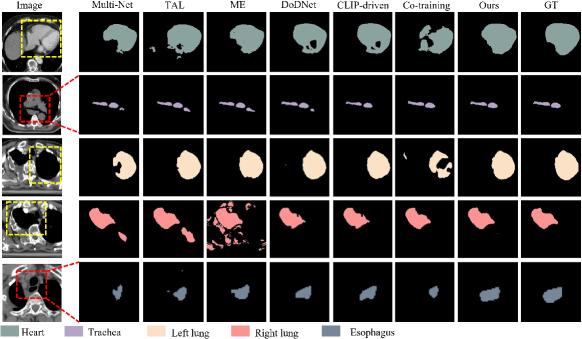

Tables I, II, III and IV present the segmentation results for the head and neck, chest, abdomen, and pelvis, respectively. Figs. 4, 5, 6 and 7 provide visualizations of these methods. The following conclusions can be drawn from these results:

Unified segmentation models generally outperform Multi-Net, as indicated by combined DSC and ASSD metrics. Among channel adjustment methods, ME outperforms TAL by leveraging non-overlapping organ annotations across datasets. The conditionally-guided DoDNet achieves sub-optimal results in the chest and abdomen but performs poorly in the head and neck and pelvis, particularly for the chiasm and parotid glands; The method also struggles to distinguish between symmetrical structures (e.g., parotid glands and humerus), as noted in COSST [4]. The CLIP-driven method performs poorly across all regions, especially for less frequent organs and structures like the chiasm. The Co-training method, based on two stage pseudo-labeling, achieves competitive results, particularly in the pelvis. Overall, our method outperforms others across all regions, especially for small organs like the chiasm and elongated organs like the esophagus. Visually, our method aligns more closely with GT, avoiding the segmentation errors of channel adjustment and the issues with symmetric structures in conditional guidance methods.

The effectiveness of our method has been demonstrated through the experiments on diverse datasets encompassing the head and neck, chest, abdomen, and pelvis, which has consistently achieved superior performance in each of these regions, surpassing the state-of-the-art methods (see Tables I, II, III and IV). Additionally, visual results show that our method’s segmentation results closely matches the ground truths (see Figs. 4, 5, 6 and 7). According to the results obtained by different methods, incorporating organ-specific priors, as evidenced in TAL [8] and ME [9], and employing pseudo-labelling through Co-training [5], effectively enriches the supervisory signals, thereby enhancing segmentation outcomes. Conditional information-guided methods excel with specific organs but struggle with smaller structures, and they are unable to differentiate between symmetric structures, such as the left and right parotid glands and the left and right humers, as shown in the fifth column of Figs. 4 and 7. Although CLIP-driven method has achieved significant success in the segmentation of abdominal organs[12], it relies on large datasets for training, and most of the images pre-trained by CLIP are natural images. Therefore, further exploration is needed to adapt this method to medical imaging.